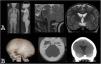

Macrocephaly is a clinical term defined as an occipitofrontal circumference more than two standard deviations above the mean. It is present in 5% of children and is a common indication for imaging studies. There are multiple causes of macrocephaly; most of them are benign. Nevertheless, in some cases, macrocephaly is the clinical manifestation of a condition that requires timely medical and/or surgical treatment. The importance of imaging studies lies in identifying the patients who would benefit from treatment. Children with macrocephaly associated with neurologic alterations, neurocutaneous stigmata, delayed development, or rapid increase of the circumference have a greater risk of having disease. By contrast, parental macrocephaly is predictive of a benign condition. Limiting imaging studies to patients with increased risk makes it possible to optimize resources and reduce unnecessary exposure to tests.